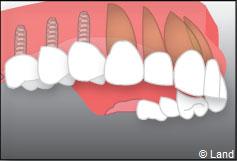

Exemple de 3 dents manquantes remplacées par 3 couronnes sur implants.

Pose des piliers prothétiques et des 3 couronnes scellées.